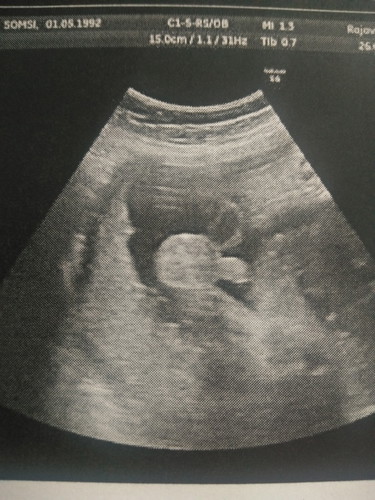

วันนี้เราพึ่งไปซาวด์มาหมอบอกน้ำหนักลูกเรา 1,864 กรัม หมอบอกตามเกณฑ์มาตรฐานดี ซึ่งอายุครรภ์เราหมอซาวด์รอบนี้อายุครรภ์ได้ 33 วีค 2 วัน ซึ่งซาวด์แต่ละรอบอายุครรภ์ ไม่เคยตรงสักครั้งค่ะ เราก็งง แต่หมอบอกลูกเราน้ำหนักตามเกณฑ์ดี อวัยวะสมบูรณ์ดีมาก ผิวหนังเต็มดี ด้วยความที่เราก็ชอบอัพเดทผลซาวด์ลูกลงเฟส เพื่อเก็บไว้เป็นความทรงจำ พอเราโพสว่าน้ำหนักลูกเราตอนนี้ 1,864 กรัมแล้วนะ แล้วพี่สาวของฝั่งแฟนเรา มาเม้นบอกทำไมน้ำหนักน้อยจัง บอกว่าเราน้ำหนักขึ้นตั้งเยอะทำไมไม่ลงลูกเลย เขาบอกลูกคนรู้จักเขาน้ำหนักตั้ง 3 โลกว่า เราก็ตอบไปว่านี่ยังไม่คลอดแค่ 33 วีคมีเวลาขุนอีกเยอะ ถ้าจะให้ 33 วีคแล้วน้ำหนัก 3 โลกว่า อิแม่ตายพอดี แล้วนางก็มาเม้นๆต่ออีกนั้นนี่บลาๆ (ปล.นางไม่เคยมีลูก นางมีลูกไม่ได้ นางรอเลี้ยงลูกเรา) ซึ่งเราก็นอยด์ว่าจะมาทั้งทำไม ในเมื่อก็บอกไปแล้วว่าหมอบอกขึ้นตามเกณฑ์มาตรฐานดี น้ำหนักกำลังดี เขาจะมาเดือดร้อนอะไรกับเรา มาเถียงมาอะไรไม่จบ เอาลูกคนอื่นมาเปรียบเทียบงี้ เราอ่านล่ะก็โมโห เราบอกให้โตตามเกณฑ์แหละดีไม่จำเป็นต้องใหญ่มากให้ออกมาโตข้างนอกเอา นางก็ชอบเอาน้ำหนักตัวเราไปเป็นที่ตั้งว่าน้ำหนักขึ้นเยอะแล้วลูกเราจะต้องตัวใหญ่ พูดแล้วขึ้น ปล.ขอระบายนิดนึงนะคะ มันสุดๆจริงๆ เขาชอบมาเม้นทำนองแบบนี้ตลอด คือคาดหวังอยากให้ลูกเราตัวโตๆจ่ำม่ำงี้ ทั้งๆที่คลอดมาๆโตข้างนอกก็ได้ วันนี้โชว์ปิกกาจู้ ไม่โชว์หน้าครับ